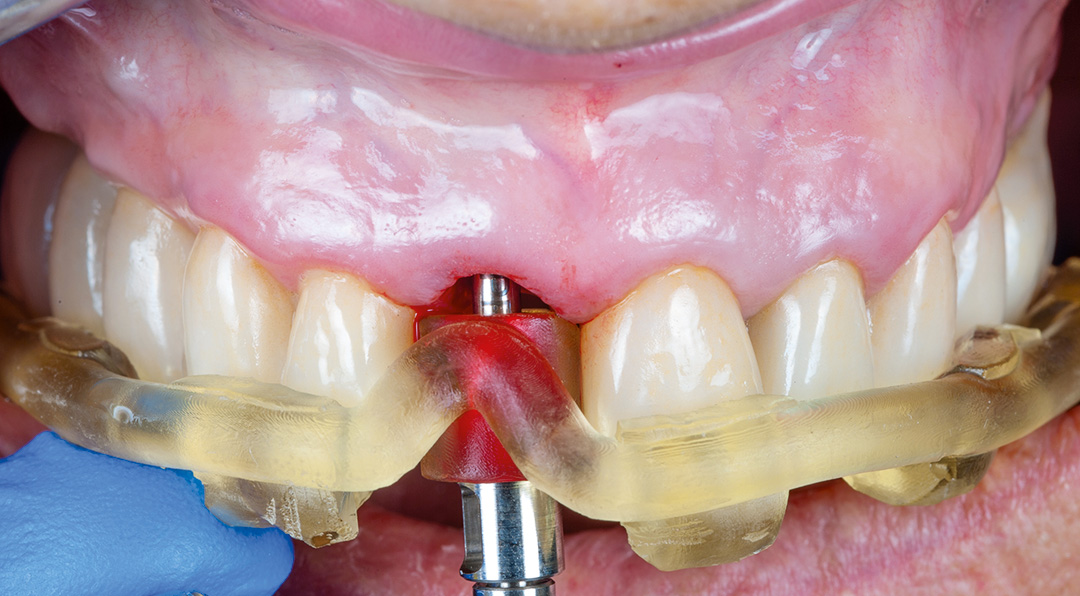

Surgery and initial outcomes

The remaining root was carefully and atraumatically extracted using a Benex® pull-out device. The surgical guide was fitted in the mouth and a CONELOG PROGRESSIVE-LINE implant with conical connection was immediately placed, torqued to above 50 Ncm for high primary stability. The space between the implant and the facial cortical bone plate was filled with MinerOss XP biomaterial and a connective tissue graft was tunnelled around the neck of the implant. This was harvested from the tuberosity, de-epithelialised, and added around the neck of the implant. The objective of this procedure was to ensure long-term papilla stability and prevent both the future collapse of the soft tissue and opening of the embrasures. This is paramount when restoring a gap in the anterior zone.

A scanbody was used to register the implant position and a provisional restoration was designed in exocad software and milled in PMMA. The temporary restoration would be used to help stabilise the connective tissue graft, while also shaping the soft tissues to develop a good emergence profile. This is an important transition stage before the final restoration.